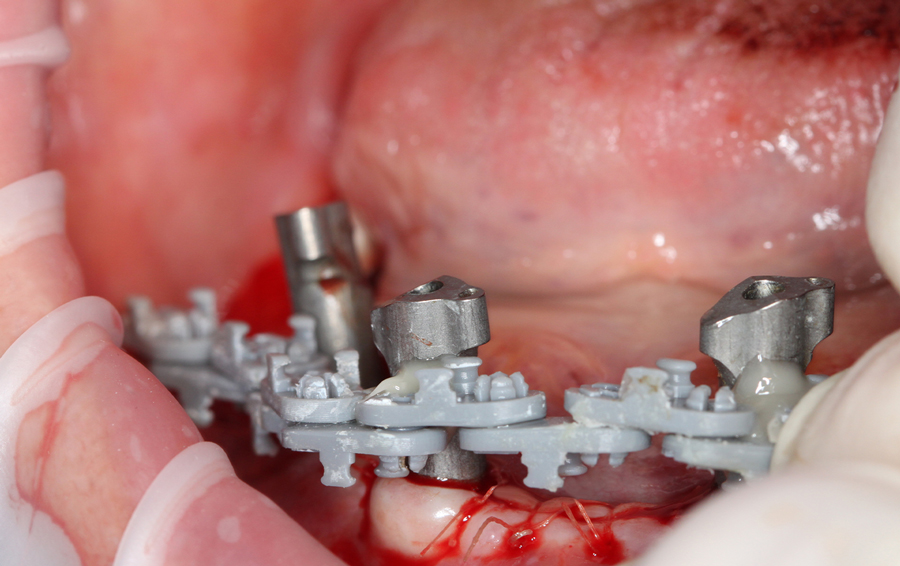

A questo punto inizia la sessione chirurgica vera e propria in cui, rimossa la protesi mobile inferiore, si posizionano 4 impianti dentali (in questo caso in chirurgia orientata) sui quali vengono avvitati i MUA. Durante l’intero atto chirurgico, gli ScanSke rimangono nei settori posteriori della bocca e saranno proprio questi a fornire l’informazione necessaria per poter costruire la nuova protesi fissa su impianti nel corretto spazio inter-arcata della paziente (Fig.6). Eseguita la sutura, si posizionano gli scanbody implantari e si esegue una scansione post-chirurgica che rileva sia gli ScanSke che gli scanbody implantari appena inseriti. Per migliorare l’accuratezza della scansione e facilitare il flusso di scansione in una cresta edentula sanguinante, gli scanbody implantari vengono solidarizzati mediante una dima di scansione (Fig. 7 a, b). Per fornire al laboratorio ulteriori informazioni, viene anche eseguita una successiva scansione della mucosa su cui poggerà la nuova protesi (Fig. 7c). Grazie alle scansioni rilevate, sia quella pre-chirurgica che quelle post chirurgiche, con gli ScanSke sempre fissi e immutati nella loro posizione, il tecnico di laboratorio riceve in remoto i files .stl delle tre scansioni intraorali, ed esegue la sovrapposizione delle stesse, ritrovandosi nell’articolatore digitale le arcate dentali nel corretto rapporto spaziale (Fig. 8), ottenuto grazie alla posizione immutata degli ScanSke e nello spazio protesico così ottenuto, progetta e realizza (in flusso 100% CAD/CAM) la protesi fissa nel rispetto dell’occlusione abituale della paziente (Fig. 9, 10, 11).

Foto successiva all’inserimento degli impianti

Fig. 6. Foto successiva all’inserimento degli impianti e al posizionamento degli scanbody implantari, nei settori posteriori gli ScanSke posizionati prima dell’atto chirurgico.